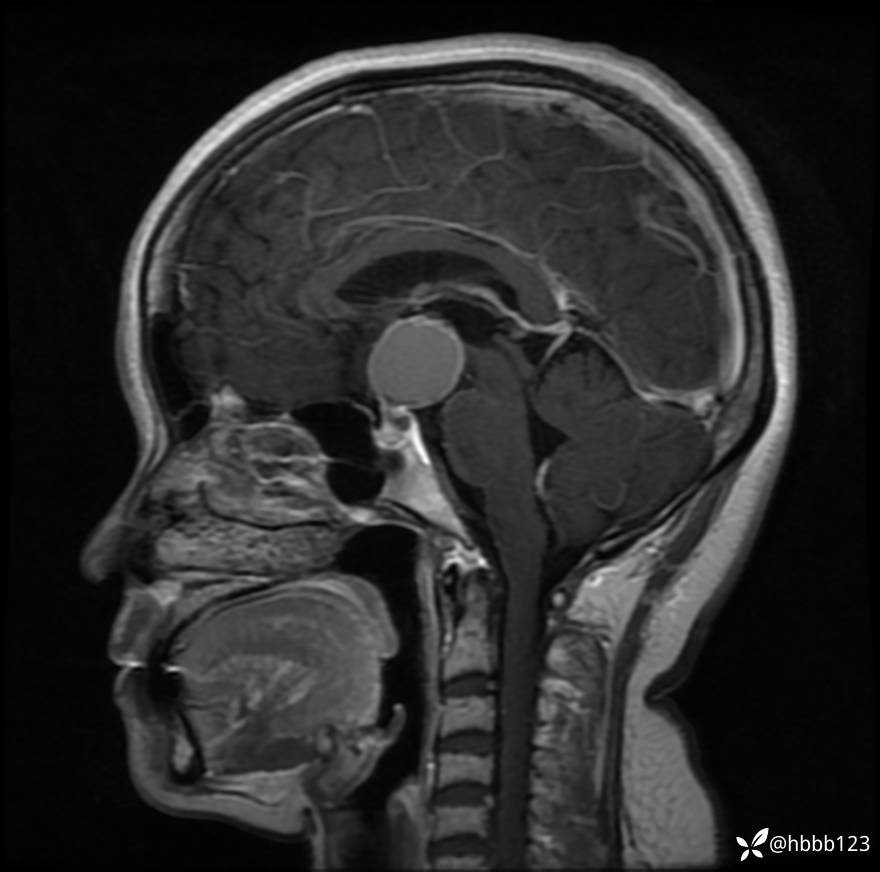

T1WI矢状位重建: